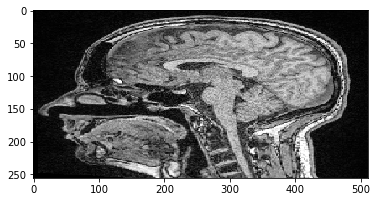

scale_factor = 2

rotation_angle = 45

transform = cle.AffineTransform3D()

transform.scale(scale_x=scale_factor)

transform.rotate_around_z_axis(rotation_angle)

cle_translated2 = cle.affine_transform(image, transform=transform, auto_size=True)

cle.imshow(cle_translated2[100])